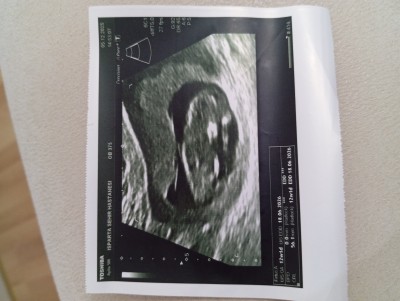

12+1 hafta anlayanlar tahmin edebilirmi çok merak ediyorum

Gebelik haftası 12+1